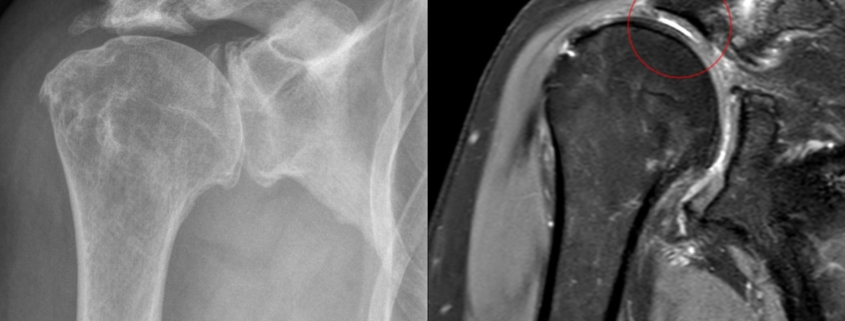

– Imaging tests: X-rays and MRIs can provide detailed images of your shoulder, allowing doctors to examine the rotator cuff muscles and joint surfaces in detail.